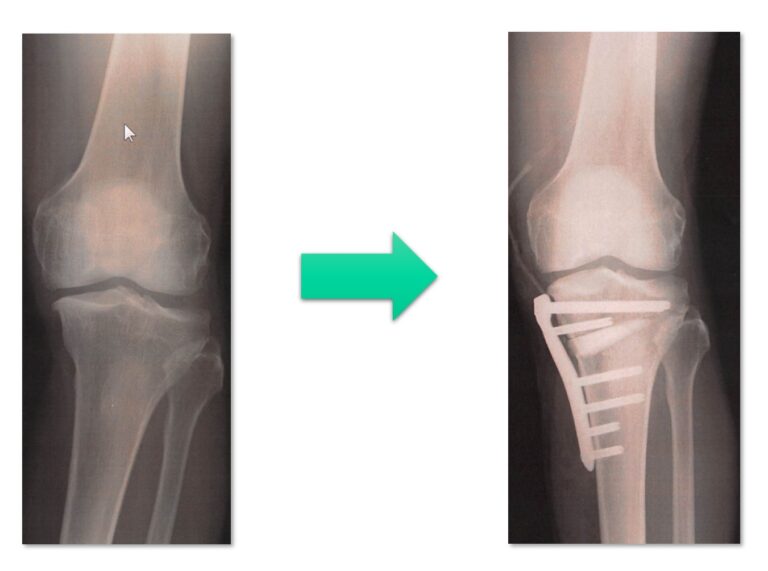

当院のHTO術式プロトコール・症例

当院のHTO術式プロトコール

立位下肢全長Xp

OWHTO術中写真

術前後のXp比較

術前後の外観比較